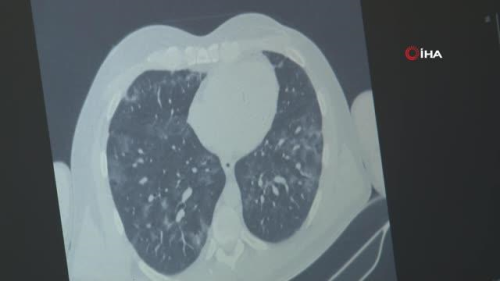

KAYSERİ - Kayseri Şehir Hastanesi Enfeksiyon Hastalıkları ve Klinik Mikrobiyoloji Uzmanı Dr. Esma Eryılmaz Eren, bu dönemde solunum yoluyla bulaşan virüslerin hepsinde artış yaşandığını söyleyerek, "Korona virüs salgını devam ederken bir yandan da epeydir vaka görmediğimiz influenza hastalarımız artan sıklıkla görülüyor" dedi. Kayseri Şehir Hastanesi Enfeksiyon Hastalıkları ve Klinik Mikrobiyoloji Bölümü'nden Uzman Dr. Esma Eryılmaz Eren, bulaşıcı bir solunum yolu hastalığı olan influenza hakkında bilgiler verdi. İnfluenzanın görüldüğü vaka sayısında bir artış yaşandığını kaydeden Eren, "Kış aylarının gelmesiyle birlikte insanların daha çok kapalı ortamlarda birlikte vakit geçirmesiyle beraber solunum yoluyla bulaşan virüslerin hepsinde artma görüyoruz. Bir yandan korona virüs salgını devam ederken bir yandan da epeydir vaka görmediğimiz influenza hastalarımız artan sıklıkla görülmektedir. Maskenin önemi halen devam ediyor. Biraz rahatlamayla maske kullanımı ve insanların kalabalık ortamda vakit geçirme süresi arttığı için solunum yoluyla bulaşan hastalıklar artıyor. Bunlardan en önemlisi influenzadır. Hasta insanların hapşırması ve öksürmesiyle havada asılı kalan damlacıklarla bu virüs bulaşıyor. Maske kullanımına da dikkat edilmediği zaman aldığımız nefesle beraber enfekte oluyoruz. Ateş ve öksürük ile devam ediyor. Ev içinde de bulaş mevcut. Ateş ve öksürük nedenli poliklinik başvurularımızda artış var. Bu şekilde vakalarımız artmış durumdadır" ifadelerini kullandı. "Korona virüs aşısı influenzadan korumaz" Korona virüsle influenzanın klinik durumda ayırt edilmesinin oldukça zor olduğunu dile getiren Esma Eryılmaz Eren, vatandaşlara da uyarılarda bulunaral, şunları söyledi: "Bu virüsün yıllardır uyguladığımız kendi aşısı var ama influenza vakalarını çok görmediğimiz için bu sene aşı sayısı oldukça azaldı. Bununda etkisiyle influenza vakalarımız epey artmış durumda. Domuz gribi influenzanın bir tipidir. Kuş gribi de influenzanın bir tipidir. Bu virüslerin genel ismi influenza virüsüdür. Korona virüste, influenza da solunum yoluyla bulaşır. Klinik durumda ayırt etmek oldukça zordur. Her ikisi de akciğer tutulumu ve ateş yapabilir. İnfluenza da eklem ağrılarını biraz daha fazla görüyoruz. Tat ve koku kaybı influenza da çok beklediğimiz bir durum değil. İnfluenza özellikle gebelerde, 65 yaş üstünde, KOAH'ı ve diyabeti olan hastalarda daha ağır seyreder. Buna dikkat etmek gerekir. Vatandaşlarımız maske kullanmaya dikkat etsinler. Kapalı ve kalabalık ortamlardan mümkünse uzak dursunlar. El hijyeninin önemi de halen devam ediyor."